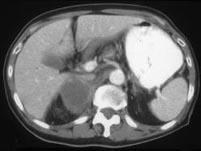

问题 男,75岁,右侧胸痛伴咯血3个月余,胸部CT提示右侧中央型肺癌,请结合图像,作出诊断 ( )

选项 A、右侧肾上腺癌 B、右侧肾上腺嗜铬细胞瘤 C、右侧肾上腺转移瘤 D、右侧肾上腺腺瘤 E、右侧肾上腺囊肿

答案 C